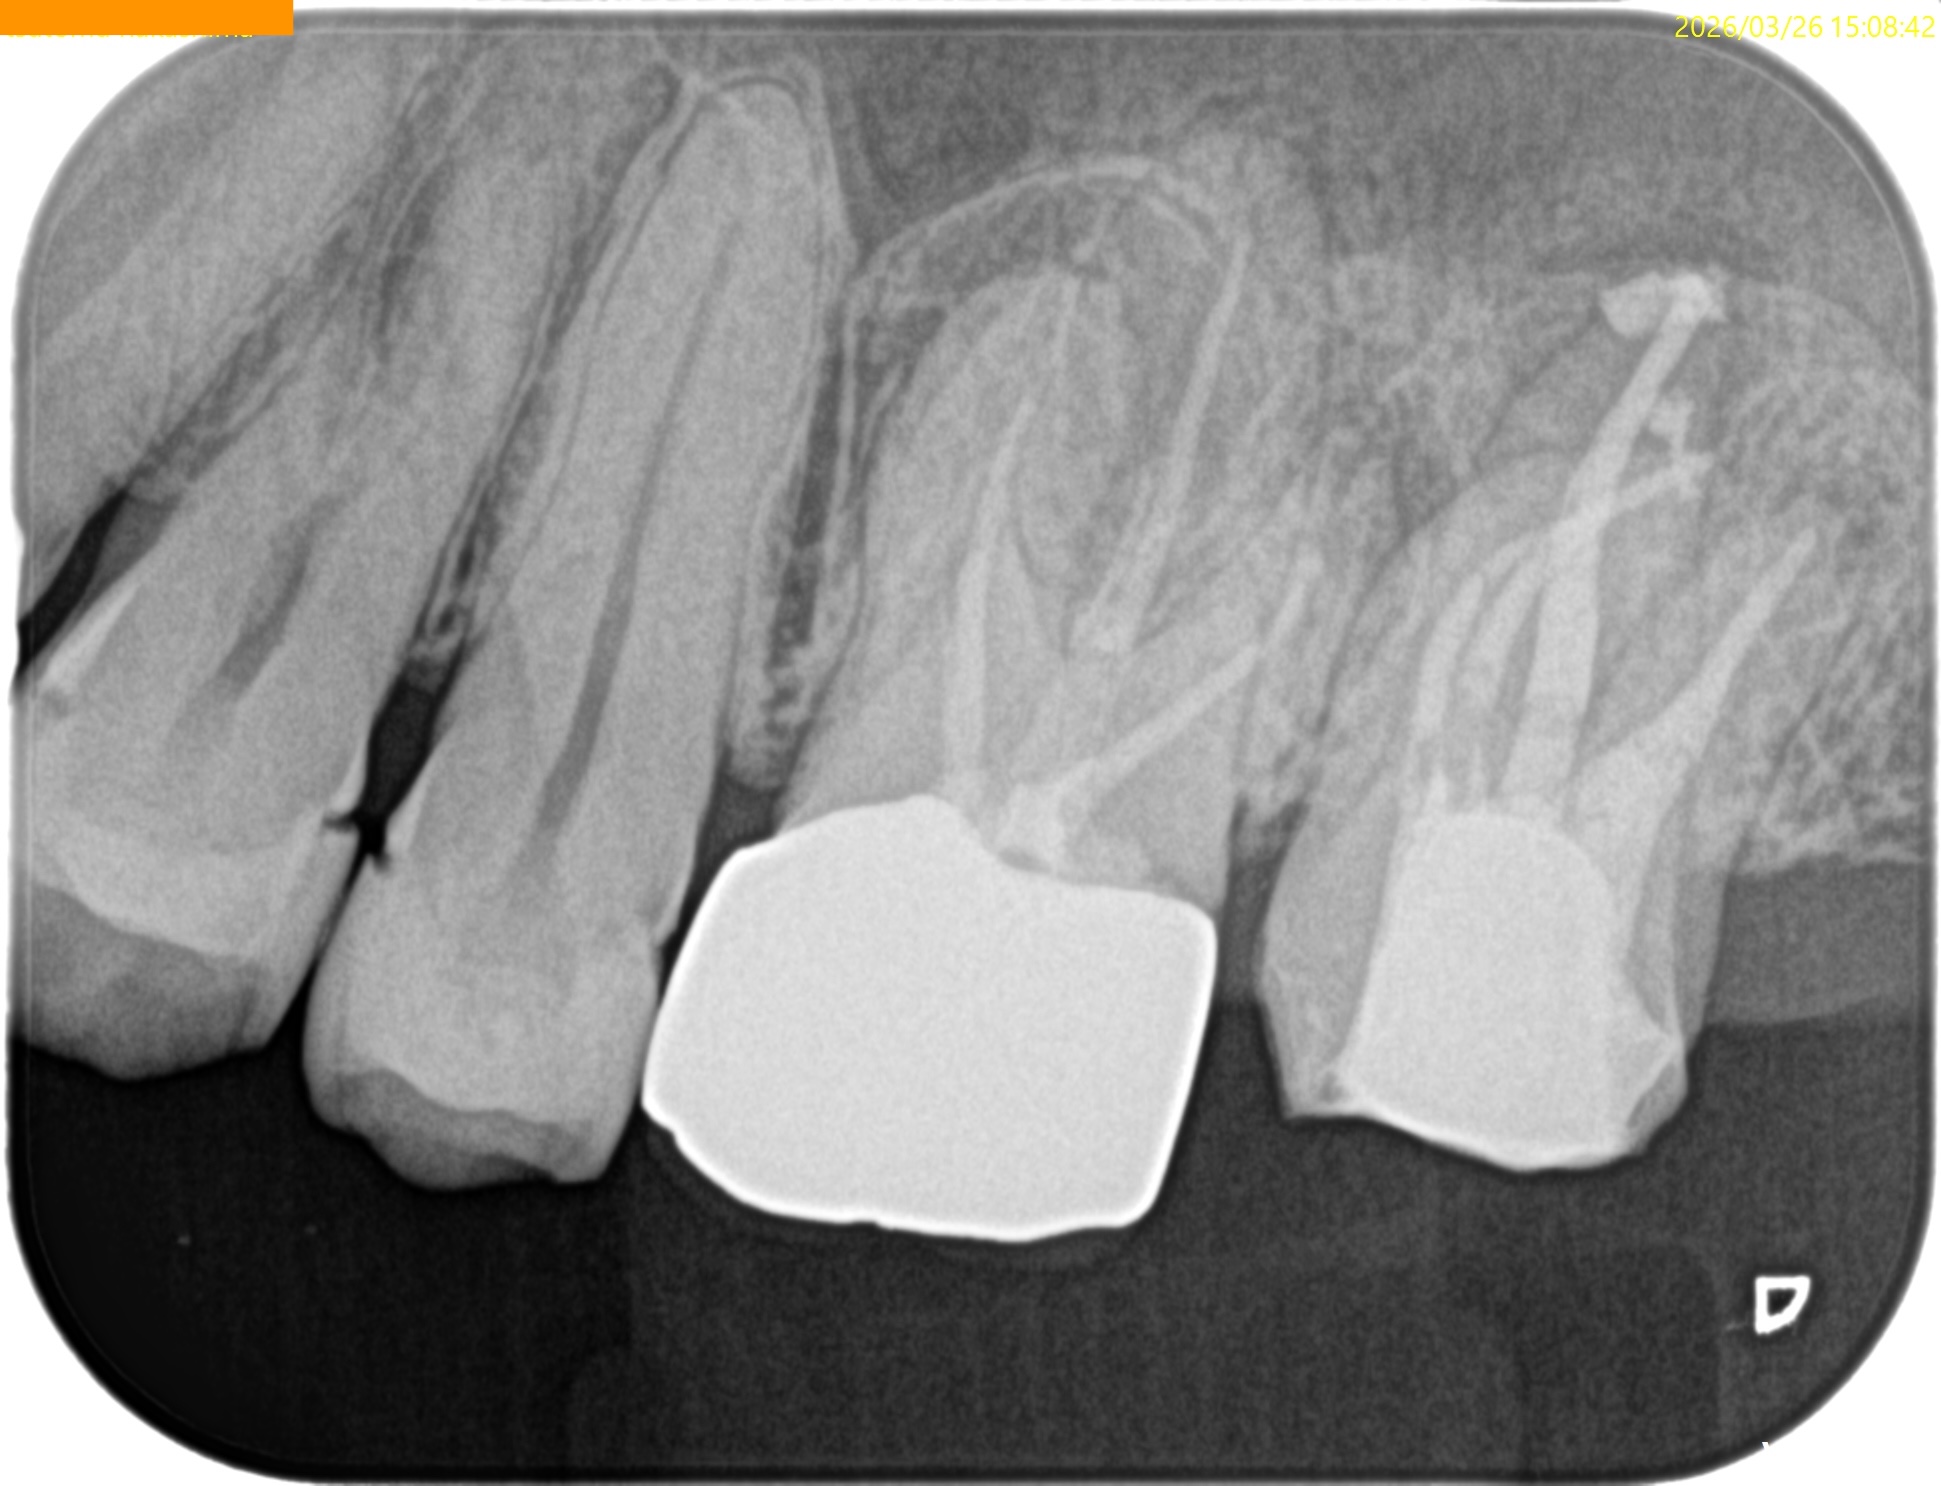

術後のPA, CBCTは以下である。

MB1

MB2

DB

P

問題はないだろう。